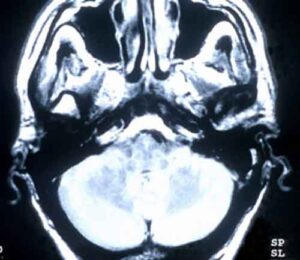

Il cervello dei malati psicogeni segue altre dinamiche di funzionalità

Le malattie psicogene, in passato conosciute come patologie isteriche, possono portare a sintomi molto gravi come crampi dolorosi e paralisi,...